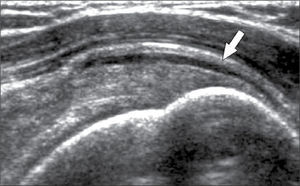

El tendón de Aquiles por sus características anatómicas y función particulares, a veces genera un examen ecográfico propio. Puede manifestar patología de distintas maneras, además de la tendinopatía similar a los otros tendones, incluso cálcica, en el tendón de Aquiles se puede encontrar engrosamiento del peritendón (no tiene vaina sinovial), aumento de vascularización, bursitis periaquilianas, alteraciones en la grasa de Kager, roturas parciales intrasustancia o completas en tercio medio o en la unión miotendínea con el tríceps sural (figura 11) (28).